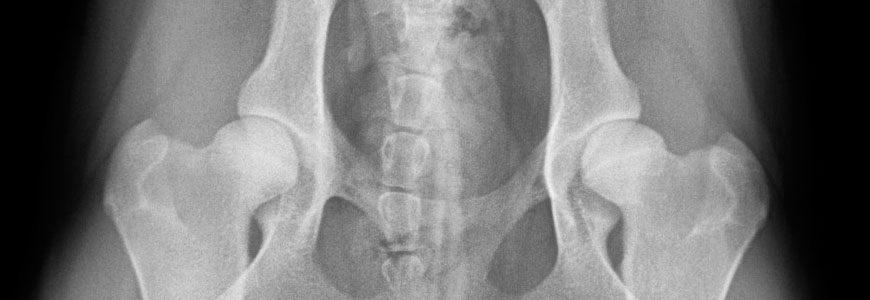

HHD Aufnahme Hund gebeugt

Bei der HD liegt eine Dysplasie vor - eine Fehlbildung also - dabei passen Kopf und Pfanne nicht richtig zueinander. Es kann sein, daß die Pfanne zu flach ausgebildet ist und infolgedessen der Kopf aus der Pfanne herausrutscht und an deren Enden scheuert.

Oft aber ist die Pfanne normal ausgebildet, jedoch der Kopf zeigt eine Mißbildung und scheuert in der normal geformten Pfanne.

Eine beginnende HD äußert sich in zunehmenden Schmerzen bei Spaziergängen, der Hund will nicht mehr weit laufen, setzt sich öfter hin, schreit beim Spielen ab und zu auf und zeigt einen instabilen Gang. Beim Vorführen der Hintergliedmaße wird das Becken in Richtung der vorgeführten Gliedmaße seitwärts bewegt . Bei Bewegungen des Gelenkes kann ein hörbares Knacken, Klicken oder Knirschen des Gelenks auftreten.Vermutete Mißbildungen, die nicht so gravierend sind, daß sie direkt auffallen, kann man durch eine Röntgenaufnahme eindeutig feststellen. Diese muß unter einer Kurzzeitnarkose erfolge